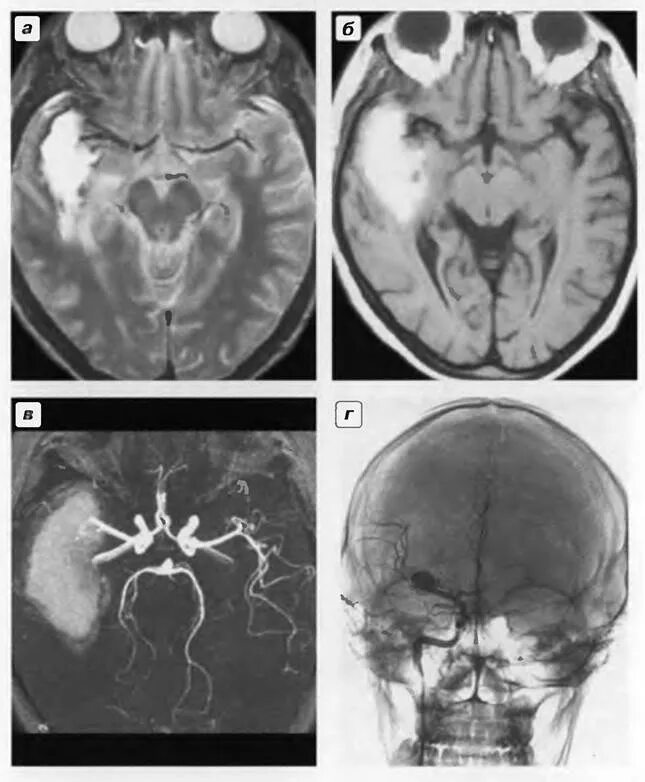

Аневризма сосудов головного мозга причины